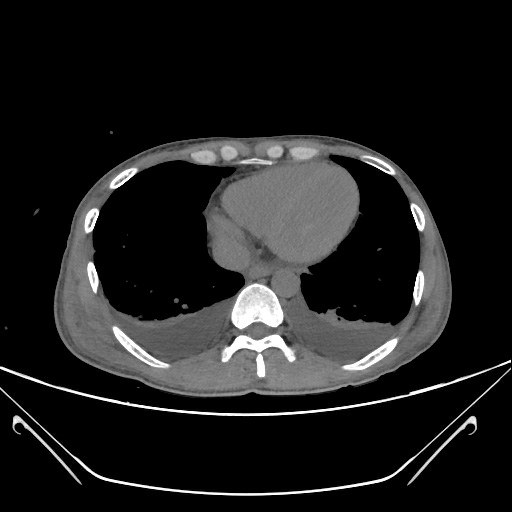

【全腹CT平扫】:急性胰腺炎:胰腺肿胀,胰周渗出、少许积液,局部肠系膜浑浊,双侧肾周筋膜增厚,双侧结肠旁沟及盆腔少许积液。